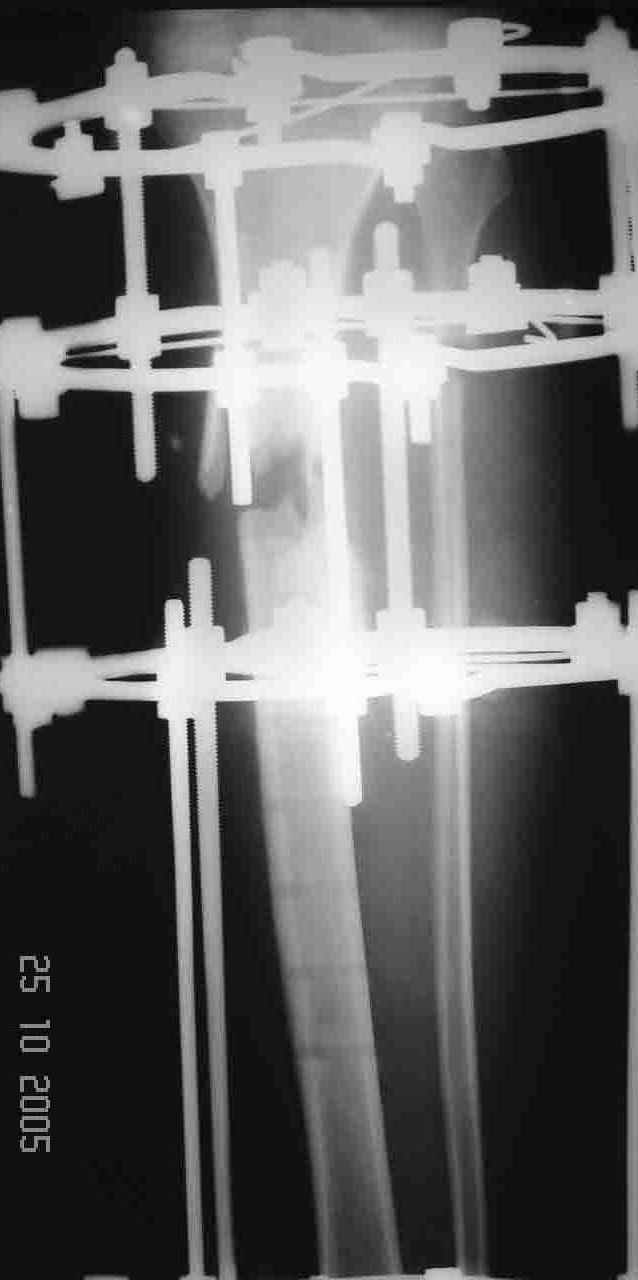

На операции после удаления пластины вывалился промежуточный свободный фрагмент,оставлять его посчитали нецелесообразным. После его удаления вскрыли костномозговой канал, зашили рану и наложили аппарат. После заживления раны концы отломков сблизили. Возможно, всё это же можно было бы сделать одномоментно и на стержне. Но как то мы не решились забить гвоздь при наличии большой раны и костного дефекта. Сейчас 2 недели после операции, больной ходит при помощи костылей с одинаковой нагрузкой на обе ноги. Укорочение в итоге 1,5 см. Обязуюсь показать снимки через пару месяцев.